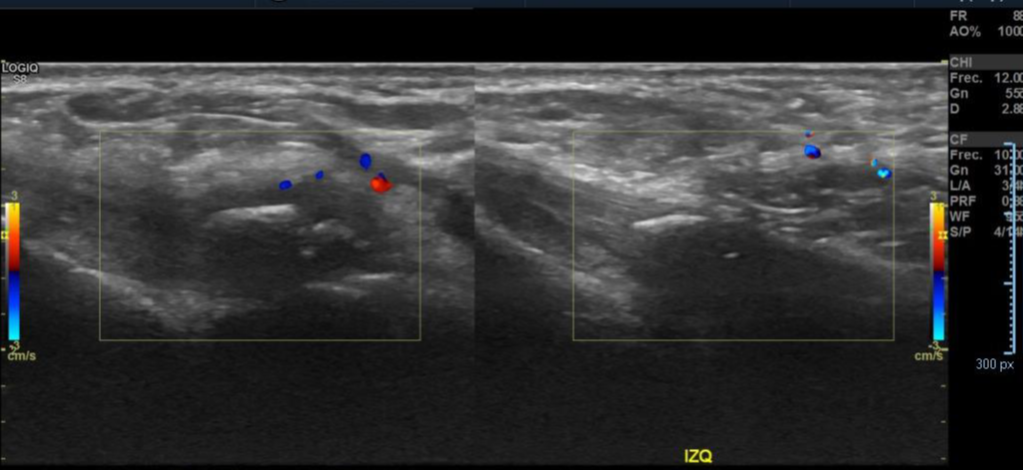

• Paciente masculino de 53 años. Presenta dolor en cara lateral del pie derecho, pie izquierdo normal.

Antecedentes: Dolor en cara lateral del pie y tobillo en relación a actividad deportiva.